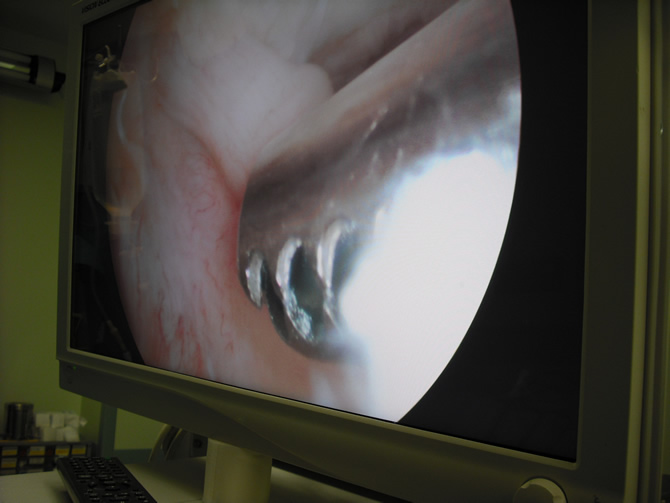

Εικόνα 1: Ρήξη πρόσθιου χιαστού συνδέσμου γόνατος